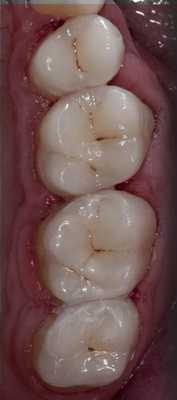

Главной целью реставрации жевательных зубов является, прежде всего, функциональная реабилитация. Функциональность, в свою очередь, обусловлена анатомической правильностью и точностью изготавливаемой конструкции. Выпуклая и рельефная жевательная поверхность образует множественные точечные контакты с зубами-антагонистами, равномерно распределяя окклюзионную нагрузку. Контактные точки должны быть небольшими по площади, обеспечивая быстрое размыкание зубов при экскурсионных движениях.

Широкие и плоские смыкающиеся поверхности с большей вероятностью останутся в контакте при движениях нижней челюсти. При этом возникает трение, приводящее к более выраженному износу зубов и реставраций и снижению жевательной эффективности. Едва ли кто-нибудь станет оспаривать необходимость точного воспроизведения жевательной морфологии при проведении реставрации. Однако достижение этой цели для подавляющего большинства докторов сопряжено со значительными трудностями. Одной из самых распространенных проблем является то, что врачу после кропотливой и длительной моделировки жевательной поверхности приходится нещадно спиливать бором все бугорки и фиссуры на этапе интеграции зуба в окклюзию.

Вся красота, которую воссоздает специалист, превращается в итоге в бесформенную, неэстетичную и малофункциональную «лепешку». В стоматологической литературе описано большое количество всевозможных методик, позволяющих избежать подобных сложностей (метод циркуля, ориентировка на рядом стоящие зубы, окклюзионный компас, всевозможные схематизации, упрощенные алгоритмы построения и т. д.). Однако все эти решения дают лишь приблизительные результаты. Те подходы, которые будут рассмотрены в этой статье, призваны в значительной степени облегчить работу врачей и позволят изготавливать высокоточные реставрации. Главной идеей, взятой в качестве основы для данного подхода, является то, что в зависимости от степени разрушенности зуба используются соответственно разные методологические вариации восстановления. Следует, однако, отметить, что эти методики ориентированы на работу с витальными зубами, то есть в условиях, благоприятных для формирования прочного адгезивного соединения. По степени разрушенности можно выделить три условных класса (классификация разработана автором статьи).

Среди клинических случаев этой категории чаще всего встречаются глубокие кариозные полости и несостоятельные пломбы. Главной особенностью второго класса является то, что при довольно высокой разрушенности — до 50 % жевательной поверхности — все еще сохраняются основные очертания бугорков, гребней, части валиков и т. д. Имея в распоряжении подобные ориентиры, мы можем легко продолжить внешние контуры сохранившихся окклюзионных элементов и получить жевательную поверхность, очень близкую к оригиналу. Для этого используется традиционная методика послойной реставрации, без каких-либо изменений. Единственным дополнением, которое могло бы помочь сделать реставрацию более удобной, является применение моделировочных инструментов в определенной последовательности.